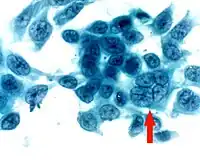

- Corneal smears or impression cytology specimens can be analyzed by culture, antigen detection, or fluorescent antibody testing. Tzanck smear, i.e.Papanicolaou staining of corneal smears, show multinucleated giant cells and intranuclear inclusion bodies, however, the test is low in sensitivity and specificity.